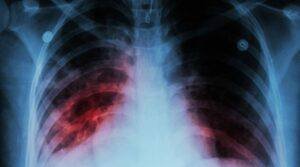

Menos casos de tuberculose em Cabo Verde

“No ano 2021, a situação em termos de tuberculose em Cabo Verde manteve-se, pois, nos anos anteriores tínhamos recebido notificações à volta de duzentos, duzentos e tal casos, mas este...